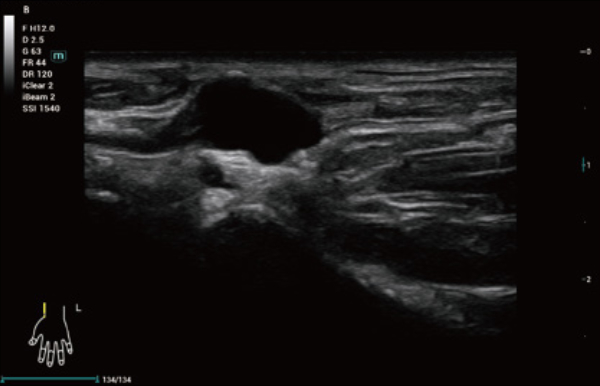

No matter your routine is in hospitals, clinics, or you are honing skills in General Imaging applications, women's health care or cardiovascular specialties, you will find highly powerful tools available on this series to keep you stay ahead.

Comprehensive Imaging Solutions Powered by ZST+

The ZST+ platform is an extraordinary innovation, representing an ultrasound evolution. Transforming ultrasound metrics from conventional beam-forming to channel data based processing. It overcomes the traditional trade-off limitation among spatial resolution, temporal resolution and tissue uniformity, delivering exceptional image quality for infinite imaging solutions with non-stop improvements.